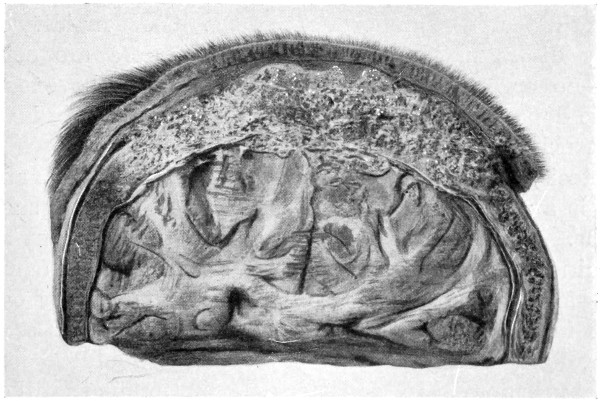

Fig. 20. An Occipital Cephalocele. (For further description, see text.)

Sincipital cephaloceles are usually quite small, but the occipital variety and those situated in[35] the region of the anterior fontanelle frequently attain a great size (see Figs. 20-22).

Fig. 22. An Occipital Cephalocele. (For further description, see text.)

The child was 3 months old, and presented a tumour, the size of an orange, situated between the occipital protuberance and the nape of the neck. The mass was pedunculated, the stalk being about the size of a four-shilling piece in diameter. It was soft, translucent, irreducible, and swelled up on coughing. An attempt at removal was carried out, and, after incising the outermost layers, three ounces of cerebro-spinal fluid escaped. A second tumour was then found occupying the base of the swelling. This was also punctured, more fluid escaping. Both sacs were cut away and the wound sewn up. Death occurred on the third day, preceded by convulsions, retraction of the head and neck, and high fever. The autopsy showed that the fontanelles were widely open, the anterior measuring 4 inches from side to side and 21⁄2 from before backwards. The bones of the vault were markedly thinned. In the subdural space there was a quantity of fluid, and the cerebral substance was soft and diffluent, the convolutions flattened, and the ventricles distended. There was a broad gap in the occipital bone, extending downwards into the foramen magnum, and in this situation the cerebellum had bulged backwards into the protruding mass. (See Fig. 22).